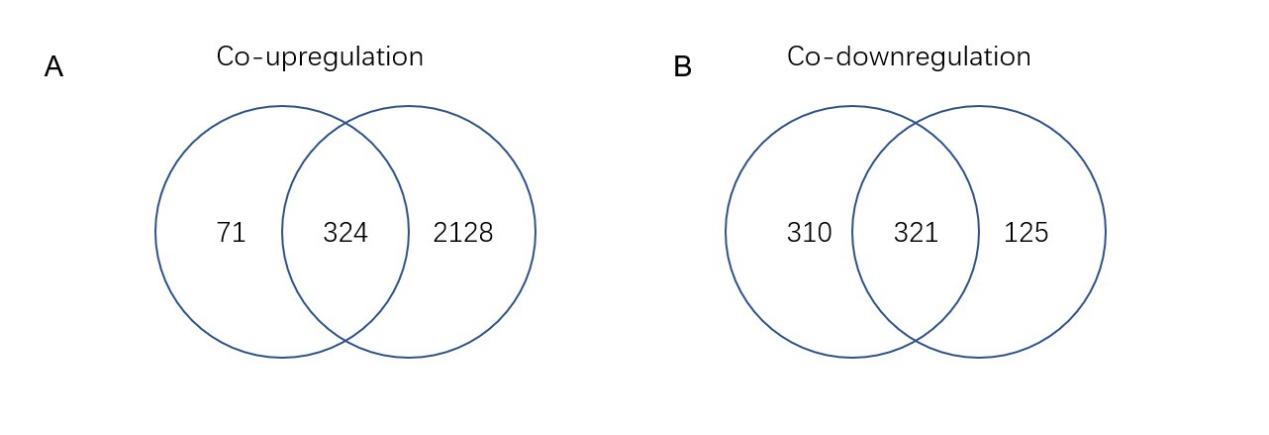

The intersection of DEGs from the TCGA and GEO databases revealed 324 co- upregulated genes (Figure 3A) and 321 co-downregulated genes (Figure 3B). These common upregulated and downregulated genes were further analyzed for their interaction networks using the STRING database, revealing widespread gene interactions. The DBSCAN clustering algorithm identified 12 clusters for upregulated genes and 24 clusters for downregulated genes. The most central cluster in the upregulated genes was designated as cluster 1, serving as a hub gene, while the most central clusters in the downregulated genes were clusters 1 and 2, which were also considered hub genes. Figures 4 and 5 illustrate the clustering of interaction proteins and their network distributions. A total of 94 hub genes showed increased expression, while 37 showed decreased expression.